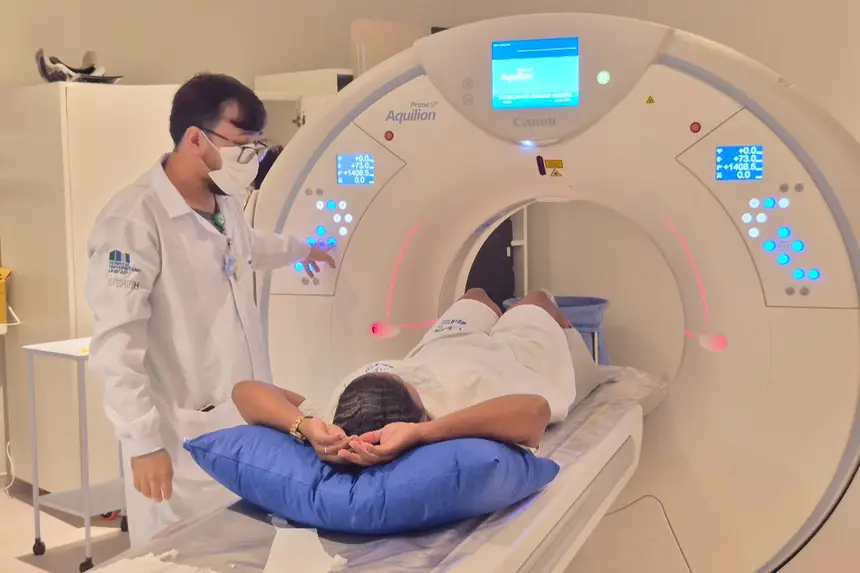

A usuária do SUS Emilly Nicoly Costa Soares foi uma das primeiras a utilizar o novo equipamento de tomografia.

“Foi muito bom estrear o equipamento, porque eu estava esperando há muito tempo. Meu marido está me acompanhando e sabe o quanto foi difícil conseguir. Agora deu tudo certo, graças a Deus. Foi um sucesso. O ambiente é frio, mas faz parte”, relatou a paciente.

O Centro Tecnológico é composto por aparelhos de ressonância magnética, tomógrafo computadorizado, equipamento de mamografia, raio X telecomandado e densitometria óssea.

Os equipamentos foram adquiridos por meio de contratação e fazem parte do plano de qualificação de exames por imagem.